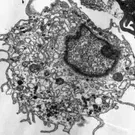

Chaîne respiratoire